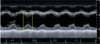

Which phase of the cardiac cycle is represented within the yellow brackets? a) ventricular diastole b) vetricular systole c) atrial diastole d) atrial systole

d) atrial systole